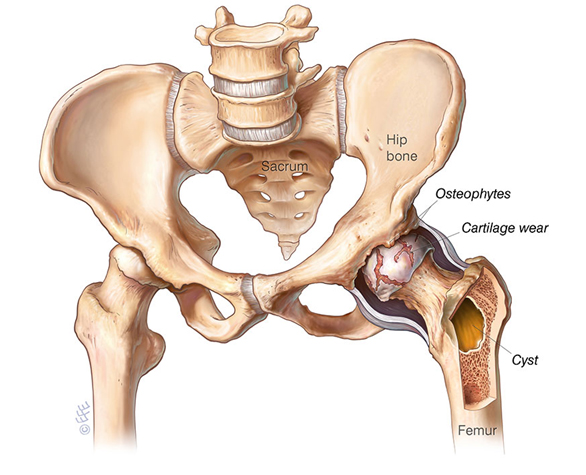

Hip Osteoarthritis is marked by progressive cartilage degradation, leading to chronic hip pain, stiffness, and functional limitations, particularly in older adults.

Clinical Indicators and Diagnosis

Patients typically experience a gradual onset of hip pain and stiffness, which limits mobility. Imaging with X-rays and MRI is essential to assess the extent of cartilage wear, joint space narrowing, and osteophyte formation, guiding the choice of treatment.